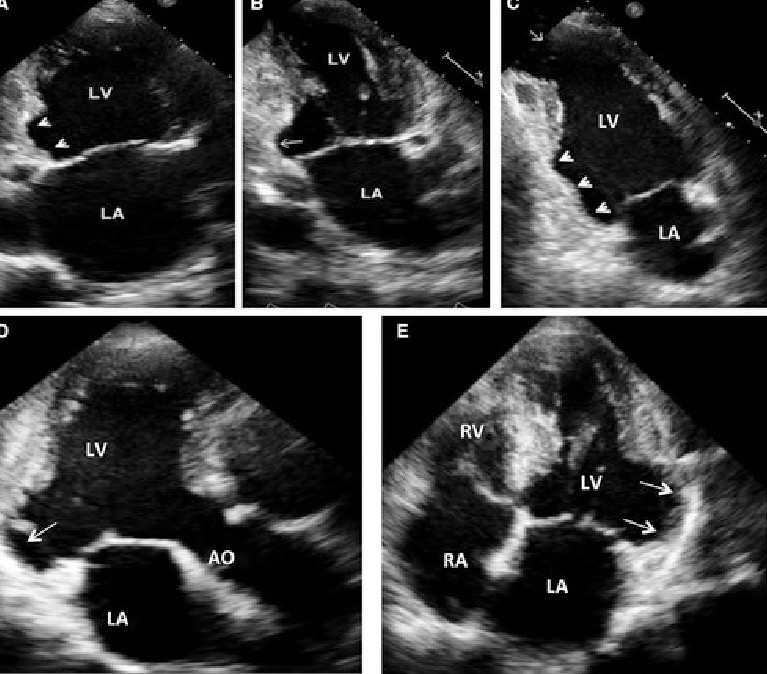

LV Noncompaction

What pathology does this echo look like?

Genetic cardiomyopathy with decreased coronary flow, thickened and trabeculated myocardium

Hypokinesis and myocardial thickening localized in apex

Takosubo CM

Cardiomyopathy described as transient LV dysfunction and expansion of the apical section & basal hyperkinesis

Broken heart Syndome

Takosubo CM is also known as ___ due to its ability to resolve on its own and symptoms occur after emotional stress